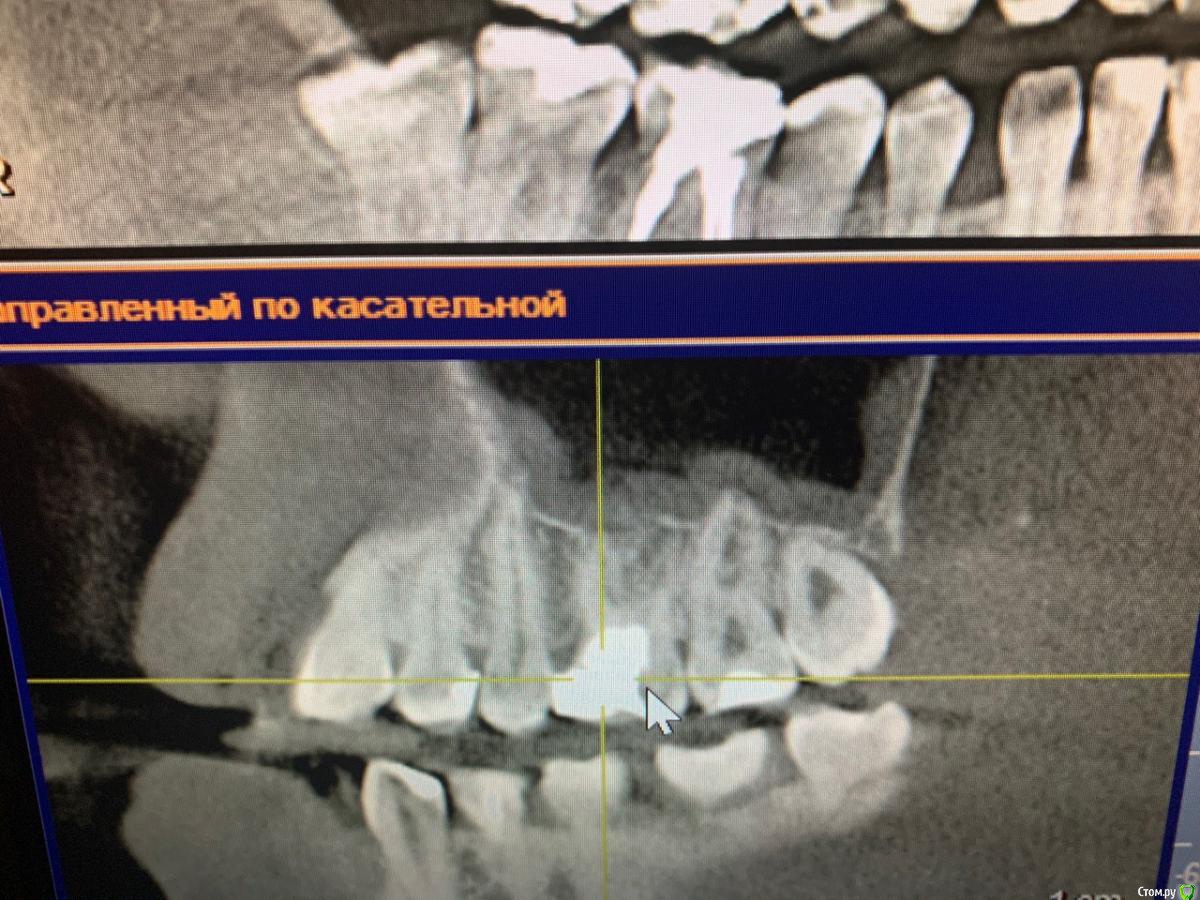

Nataly45 Опубликовано 8 октября, 2019 Поделиться Опубликовано 8 октября, 2019 Добрый вечер, мне очень нужен Ваш совет. Сразу скажу я была в 2 клиниках. и Завтра записала к члх на удаление этой 6 ки. Но очень сомневаюсь В пятницу вечером больно кусать стало, в субботу немного болело(пошла сразу к врачу сделали снимок всей челюсти) сказали надо именно удалять и именно у члх, прописали антибиотик и обезбол. Купила ,начала пить сразу. В воскресенье началась к вечеру приличная боль , о еде и речи не могло быть даже челюсть сомкнуть не могла. В понедельник,чтобы перепроверить первый диагноз удаление пошла в клинику другую,показала им снимок. Там врач предложила попробовать сохранить свой зуб играясь с лекарством,те каждые 2 недели разное лекарство в зуб закладывать,а потом резекцию. Дело это не быстрое но может сохраним зуб и поможет. Но гарантий никаких ,если что удалим. в понедельник началась мега адовая боль,ничего не помогала,звоню первому врачу,сменили антибиотик и обезбол и о чудо, мне стало легче и отлегло. Сегодня целый день не болит. но кусать больно . сказали еще что под зубом киста.Что делать? удалять или попробовать свой сохранить. Спасибо Ссылка на комментарий